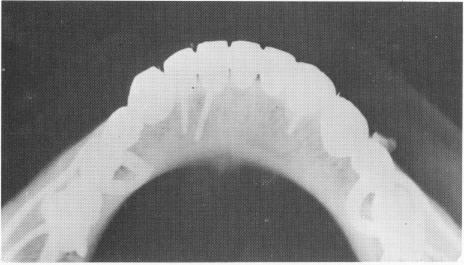

uniquely designed scalloped template with a specially chosen spring-type stress-breaker attachment was included posteriorly on either side. Anteriorly, an inverted U-shaped bar of gold, with its vertical portion fused to the base of the template, was included (Fig. 13-41). The template was cemented over the gold post copings, which already had been cemented over the two remaining bicuspid teeth (Fig. 13-42).

Fig. 13-42. The template was cemented into position, sup-ported only by two gold post copings that were cemented over the two bicuspid roots after the stabilizers were set.